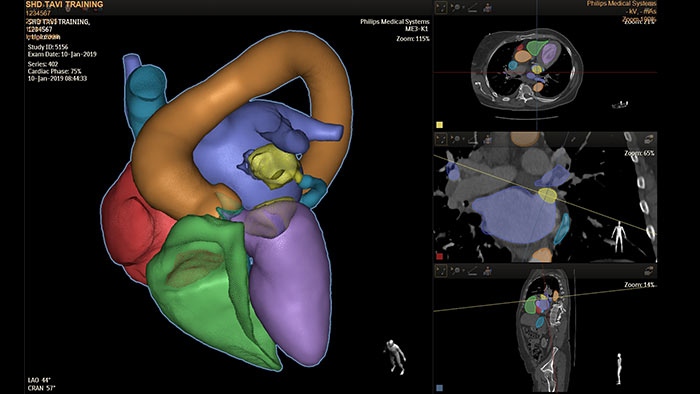

HeartNavigator ist eine Lösung für die CT-Planung und Live-Überlagerungsführung mit automatischer Herzmodellsegmentierung für mehr Bedienkomfort, Geschwindigkeit und Reproduzierbarkeit. Beim Verschließen des linken Vorhofohrs bietet HeartNavigator folgende Möglichkeiten: